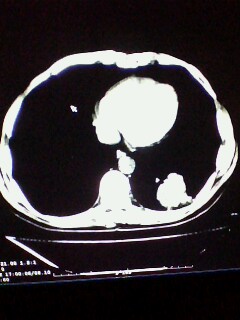

标题: CT28315:咳嗽咳痰咯血半月并胸痛 [打印本页]

标题: CT28315:咳嗽咳痰咯血半月并胸痛

左下肺肿块影,深分叶,考虑肺癌。

不排除左肺下叶周围型肺癌可能!建议穿刺活检!

考虑左肺下叶周围型肺癌。

考虑左肺下叶周围型肺癌并阻塞性肺炎。

考虑左肺下叶周围型肺癌.

考虑左肺下叶周围型肺癌